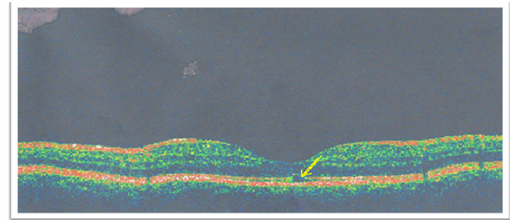

In addition, 30-2 Threshold Visual Field Tests with Standard Automated Perimetry, found paracentral scotoma in the left eye. In the red-free fundus photographs, heterogeneous foveal lesions were detected in the left retina (Figure 2). Optical coherence tomography (OCT) of the affected eye showed focal disruption of inner/outer segment junction of photoreceptor and mild thining of Retinal Pigmented Epithelium (RPE) of left macula. Retinal photoreceptor layer was disrupted, also mild reduction in the pigmented epithelium diameter was detected (Figure 3). The patient was treated with corticosteroid. Tapering doses of oral prednisolone (40 mg/day) was administered for 3 weeks. He was on 2 months follow up after the first ophthalmic visit and visual examination revealed great improvement in the later months.

Figure 3 Optical Coherence Tomography (OCT): focal disruption of inner/outer segment junction of photoreceptor and mild thickening of Retinal Pigmented Epithelium (RPE) of left macula.